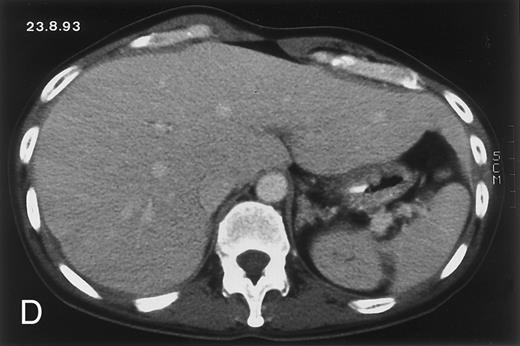

Radiologic evolution in patient A. (A) Postcontrast abdominal CT scan on March 16, 1993 shows multiple small hypodense areas in all segments of the liver, suggestive of hepatic candidiasis. Seven days previously, the patient had recovered from severe neutropenia after the first cycle of chemotherapy for AML. (B) On April 23, 6 days after the neutrophil count had dropped below 500/μL in the second cycle of chemotherapy, there is no evidence of focal lesions on postcontrast CT scan. (C) On June 18, when neutrophils were normalized for 46 days, CT scan again shows multiple small abscesses.

(D) On August 23, 15 days after the neutrophil count had dropped below 500/μL in the third chemotherapy cycle, focal liver lesions clearly decreased in size and number. (E) On September 30, 35 days after neutrophil recovery, multiple hepatic abscesses are seen (arrowhead). To show maximal extent of lesions the scan shown is at a slightly different level. (F) On June 16, 1994, 230 days after neutrophil recovery, the CT scan has normalized.